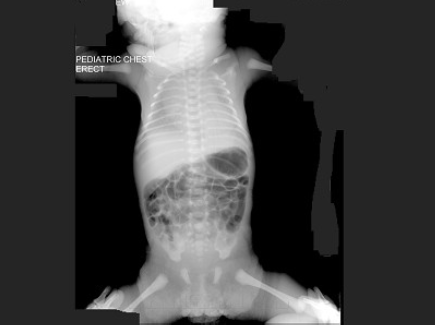

168、多项选择题

男,1岁零8个月,生长发育差,易患呼吸道感染,心悸气促,心脏正、侧位片检查如图所示,正确的描述和诊断是()

A.正位示心影向两侧扩大,心尖左移

B.肺纹理增多

C.侧位示心前间隙变窄,心后食管前三角间隙消失

D.房间隔缺损

E.室间隔缺损